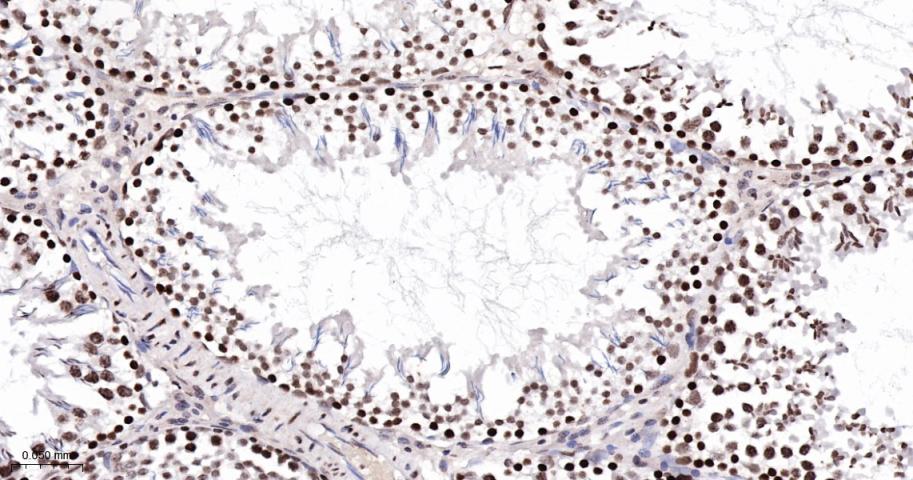

Paraformaldehyde-fixed, paraffin embedded Human Testicles; Antigen retrieval by boiling in sodium citrate buffer (pH6.0) for 15 min; The section was incubated with CDK8 Monoclonal Antibody, Unconjugated (bsm-60609R) at 1:100 overnight at 4°C, followed by conjugation to the bs-0295G-HRP and DAB (C-0010) staining.

Paraformaldehyde-fixed, paraffin embedded Rat Testicles; Antigen retrieval by boiling in sodium citrate buffer (pH6.0) for 15 min; The section was incubated with CDK8 Monoclonal Antibody, Unconjugated (bsm-60609R) at 1:100 overnight at 4°C, followed by conjugation to the bs-0295G-HRP and DAB (C-0010) staining.

Paraformaldehyde-fixed, paraffin embedded Mouse Testicles; Antigen retrieval by boiling in sodium citrate buffer (pH6.0) for 15 min; The section was incubated with CDK8 Monoclonal Antibody, Unconjugated (bsm-60609R) at 1:100 overnight at 4°C, followed by conjugation to the bs-0295G-HRP and DAB (C-0010) staining.